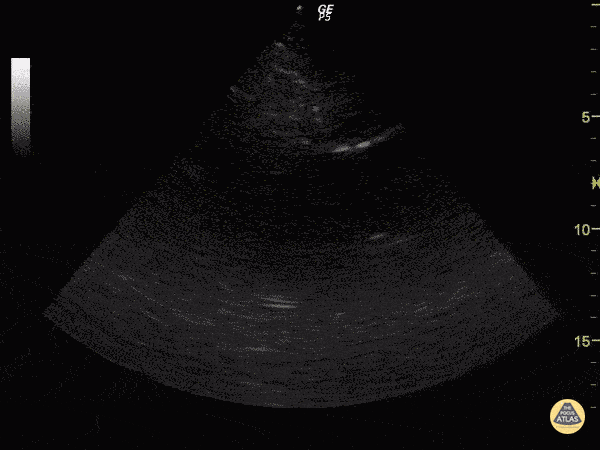

Pericardial Disease - Cardiac Tamponade in Stabbed Patient

Hematoma and relatively hypoechoic blood can be seen around the heart. Justin Bowra MBBS, FACEM, CCPU Emergency Physician, RNSH et al.